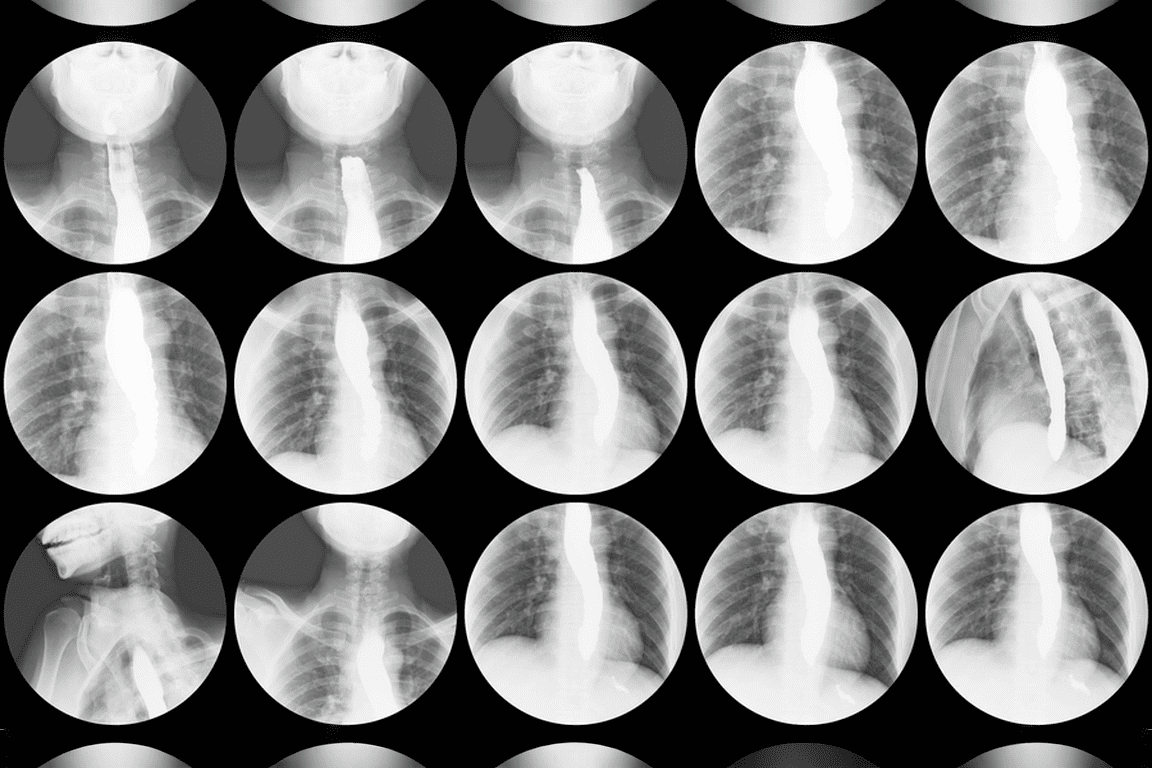

Един от най-често използваните помощни средства при подобни изследвания е т.нар. бариева каша – контрастна субстанция, която прави храносмилателната система ясно видима под рентгеновите лъчи. Но какво всъщност представлява тя, как действа и при какви случаи се прилага?

Основната му функция е да послужи като контрастно средство, тъй като барият поглъща рентгеновите лъчи много по-силно от меките тъкани в организма. Когато премине през хранопровода, стомаха и червата, бариевата каша „оцветява“ тези органи в бяло на рентгеновия екран. Така лекарят може да проследи техния релеф, форма, движение и евентуални патологични изменения.

Бариевата каша се използва основно за диагностика на заболявания в стомашно-чревния тракт. Тя намира приложение при изследвания на хранопровода, когато е необходимо да се установят стеснения, дивертикули дивертикули (малки издутини или джобове по стената на стомаха или червата), рефлукс (връщане на стомашно съдържимо в хранопровода) или новообразувания. Също така се използва при гастрография (рентгеново изследване на стомаха) за диагностика на язви, функционални нарушения или тумори на стомаха.

При изследване на тънките и дебелите черва бариевата каша дава възможност да се открият възпалителни процеси, полипи, запушвания и други патологични промени. В някои случаи се прилага двойно контрастиране, при което освен бариевата каша се използва и въздух. Това позволява още по-детайлно разглеждане на лигавицата и стените на органите.